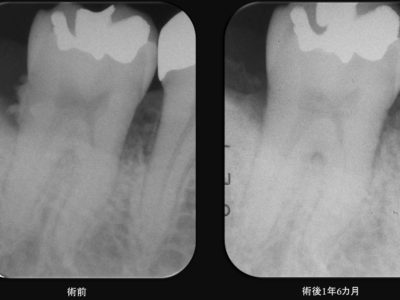

40代男性 主訴:歯茎から血が出る 初診時 レントゲン診査において青矢印部分には歯周病により、歯槽骨に垂直性の骨吸収像を認めました。 また歯周組織検査(歯周ポケットの深さの検査)において4-8㎜の深い歯周ポケットを認め、歯茎が腫れて出血しやすい状態でした。 CBCT像(3Dレントゲン診査)におい...

40代男性 主訴:歯茎から血が出る 口臭が気になる 治療前の口腔内は歯周病のため歯茎が腫れて、歯肉から出血しやすい状態でした。全顎的に4-10㎜を超える深い歯周ポケットを認めました。徹底的に歯周病の原因となる、歯面や歯根面の歯石やバイオフィルムと呼ばれる細菌巣の除去を行いました。治療後においては歯...